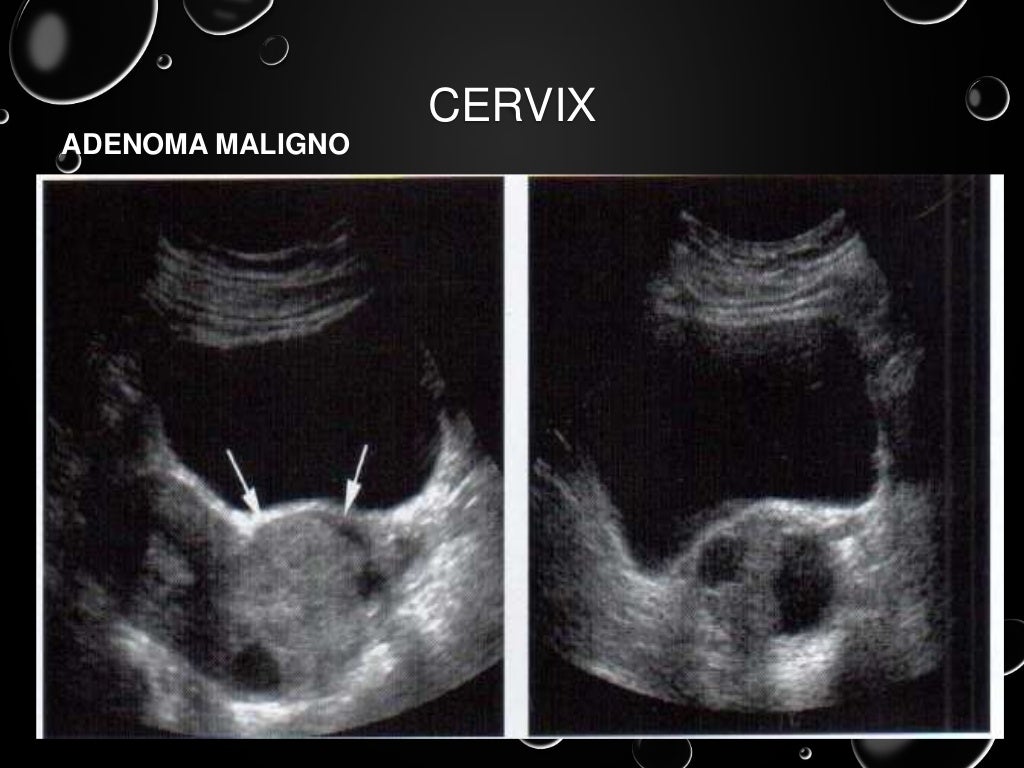

Ultrasonido pelvico

Source: es.slideshare.net